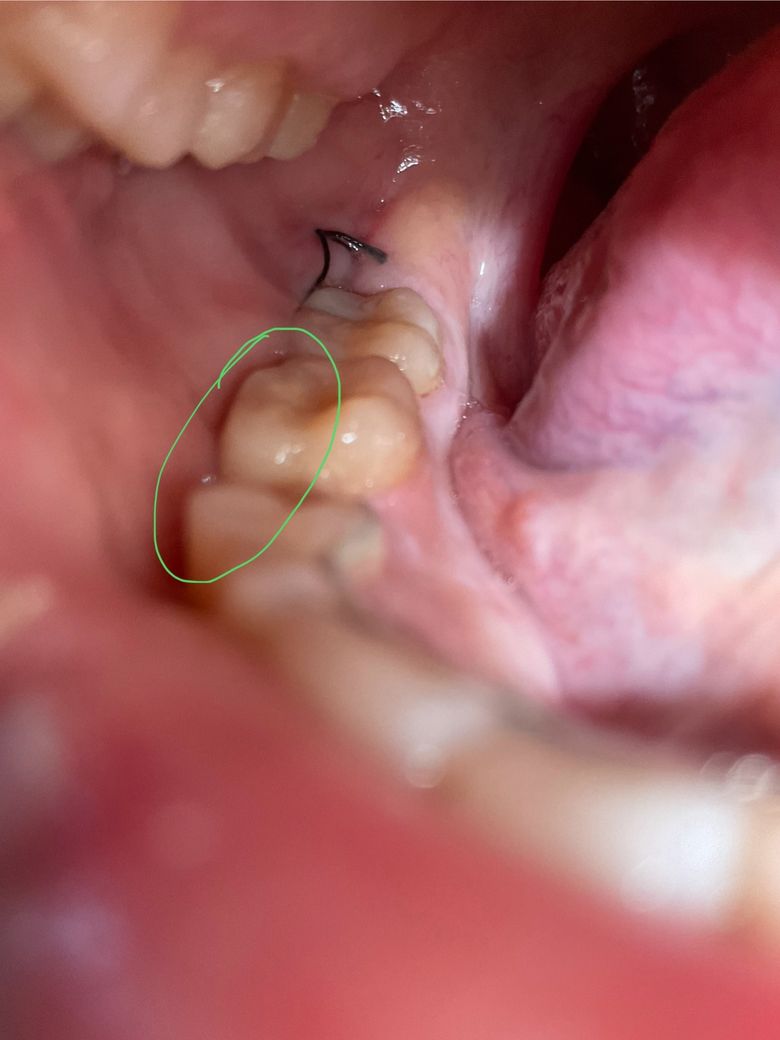

사랑니 발치 후 실밥 관련하여 궁금합니다

처음에 총 실밥 매듭 두개 지어주셨었습니다

사진상 맨 끝쪽 발치부위? 쪽에 하나 있구요 , 나머지 하나는 사진상 동그라미 친 치아들 옆에 실밥 매듭이 있는데요..

이게 정상인건지 궁급합니다! 실밥 위치가 이상해 보이는데 제가 느끼는 건지….

사진상 동그라미 친 치아들 옆에 있는 실밥 매듭쪽 건들면 약간의 피가 나고 실밥이 매듭 부분제외하곤 볼쪽으로 파묻혀있는 것이 보이기도 합니다

실밥이 이상한것 같은데

수요일날 실밥 푸는 날이라 병원에 가는데 하루 일찍 가는것이 나을까요?.

발치후에 잇몸 붓기가 빠져서 그럴수 있습니다. 문제가 잇는건 아니니 너무 걱정하지마세요.

그쪽 위치라면 수직절개부위의 봉합일 수 있을 것 같네요 아니면 봉합실이 풀려서 그럴 수도 있습니다 다만 큰 문제는 아니니 걱정마시고 예약 맞춰서 치과가세요